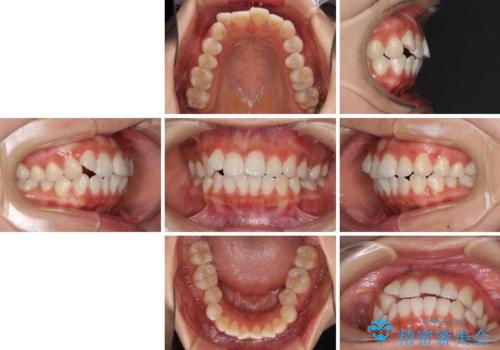

- 上下前歯のデコボコを気にして来院された患者様です。

インビザラインによる上下歯列の拡大と、IPR(歯と歯の間を削る)にるスペースの獲得により、前歯のデコボコを改善することとしました。

しっかりと装着時間を遵守してくださったので、思い通りの歯列に整えることができました。

結婚式前に終了させることができ、患者様には大変満足していただきました。